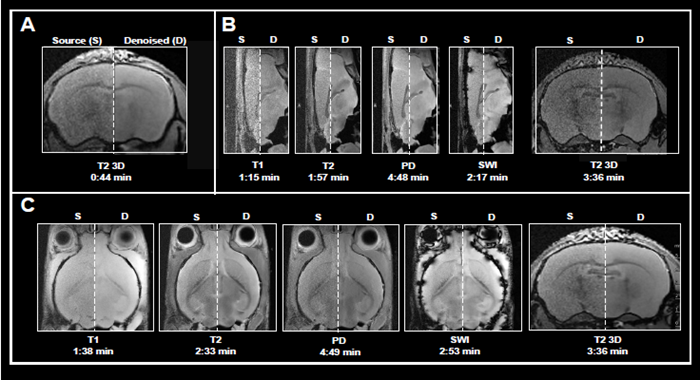

This article shows the application of Smart Noise Reduction to denoise rapid structural brain scans. Fig 4 depicts instances of ex vivo brain scans with various contrasts and orientations collected in less than five minutes. The data was collected from sensors operating at 3, 7, and 9.4 Tesla.

To accomplish the desired short acquisition time, conventional procedures produced for each system were modified to remove averaging (Fig 4A-C). This resulted in 7-15 faster acquisition times than the original protocols.

With the specified resolution, however, no averaging produced noisy images. Reconstructing the obtained data with the denoising algorithm effectively reduced noise from images and produced high-quality results.

Examples of fast brain scans

Figure 4. Examples of fast brain scans. Ex vivo data of a fixed mouse head acquired with different image contrasts, geometries and orientations. Data were acquired at A) 3 Tesla, B) 7 Tesla, and C) 9.4 Tesla. Images were reconstructed with no denoising (Source) and with a network Strong and applying 50 % pre-denoising and a denoising level of 70 % (Denoised). Image Credit: Bruker BioSpin Group